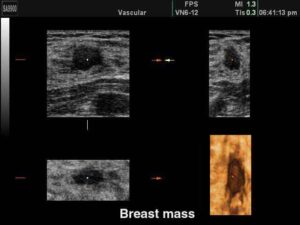

Oltre alle mammografie, le donne con un seno molto denso dovrebbero sottoporsi anche a un esame con gli ultrasuoni. Lo...